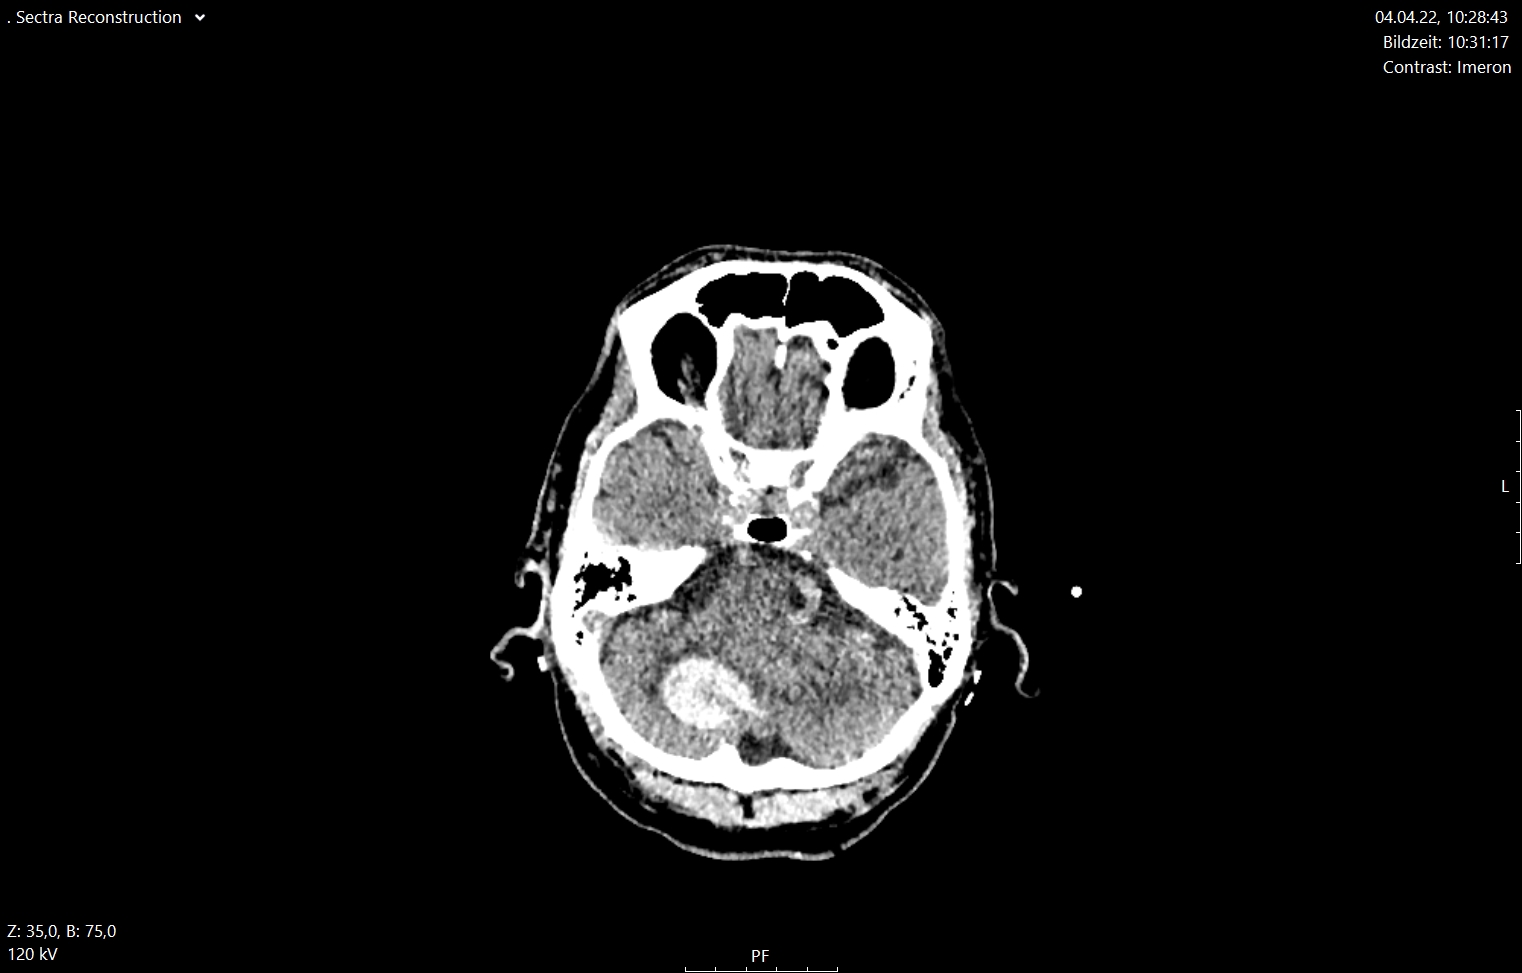

Περισσότερες λεπτομέρειες για τις ενδοεγκεφαλικές αιμορραγίες μπορείτε να διαβάσετε στο αντίστοιχο ενότητα στις παθήσεις (ενδοεγκεφαλικές αιμορραγίες)

Εδώ θέλουμε να τονίσουμε ότι σήμερα είναι δυνατό να αφαιρεθεί μια τέτοια αιμορραγία μόνο μέσω ενός ελάχιστα επεμβατικού ενδοσκοπικού χειρουργείου διάρκειας 20 με 30 λεπτών αντί για τα παραδοσιακά χειρουργεία στα οποία γινόταν μεγάλες κρανιοτομές. Στις εικόνες 12 και 13 απεικονίζονται οι προεγχειρητικές και μετεγχειρητικές εικόνες από δύο ασθενείς με ενδοεγκεφαλική αιμορραγία. Αυτές αφαιρέθηκαν ενδοσκοπικά μέσω μιας απλής κρανιοανάρτησης (1 εκ.)